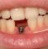

Poza Implantologie

1. Implantul dentar